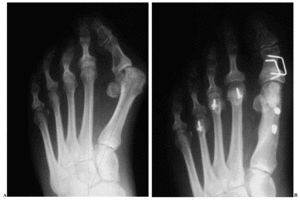

Radiológicamente, se obtuvo una mejoría significativa (tabla 2) de las deformidades al comparar las mediciones postoperatorias con las preoperatorias. Encontramos una correlación significativa (p = 0,04) entre el ángulo M1-M2 preoperatorio y la valoración clínica postoperatoria según la escala de Groulier; no encontramos correlación significativa entre la valoración clínica y el ángulo DMAA preoperatorio (p = 0,320) o el postoperatorio (p = 0,567), aunque existía una tendencia entre resultado clínico y mayor corrección de dicho ángulo (fig. 2).

Figura 2. Radiografías anteroposteriores en carga de una mujer de 49 años con hallux valgus moderado con un ángulo articular metatarsiano distal (DMAA) aumentado. A: radiografía preoperatoria. B: radiografía 12 meses después de la intervención; se aprecia una buena corrección del DMAA.